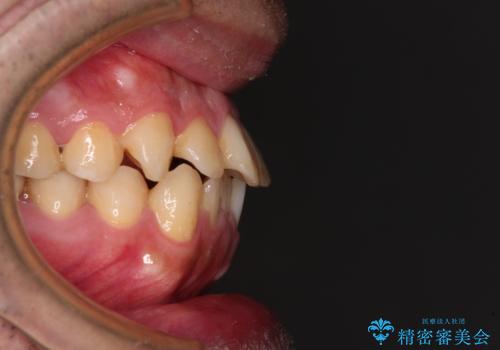

- 矯正装置

- メタルブラケット

- 治療期間

- 9ヶ月